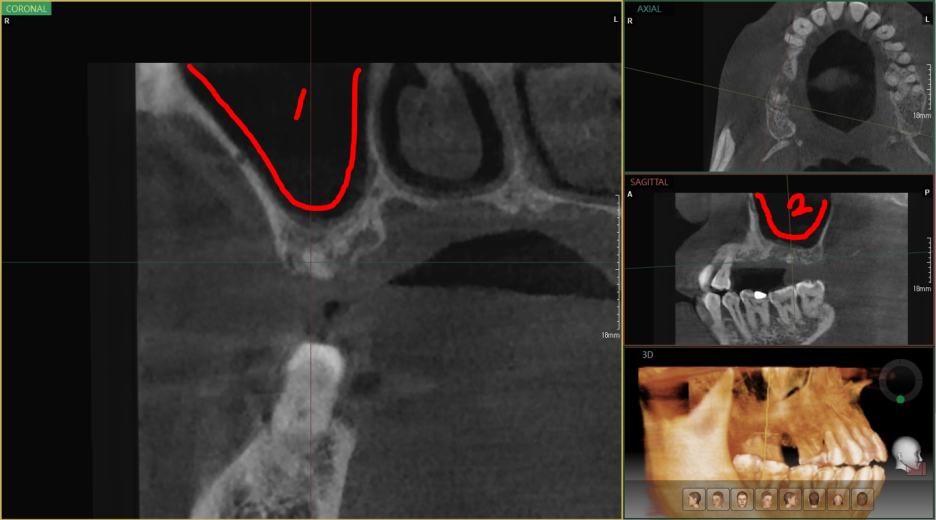

컴퓨터 단층 촬영(CT)를 통해서 조금 더 정확하게 상악동 까지의 거리를 측정하면서

심겨지는 임플란트 길이와 함께 얼마 만큼의 거상술 을 진행해야되는지 살펴봅니다.

1번 및 2번, coronal plane 및 sagittal plane 에서 뼈가 상당히 얇음을 보여줍니다.

이대로 심었다가는 큰일 나겠죠?

그래서 조금 더 신중히 진단을 내리게 됩니다.

화면에서 보실 수 있는 3D 모형은 디오나비 라는 디지털임플란트 시스템 구현 화면입니다.